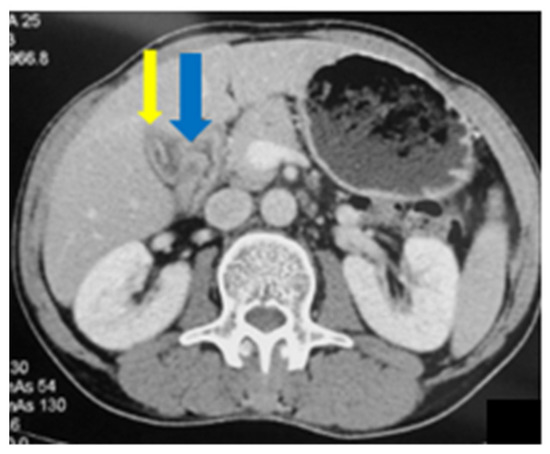

2.1. Case 1